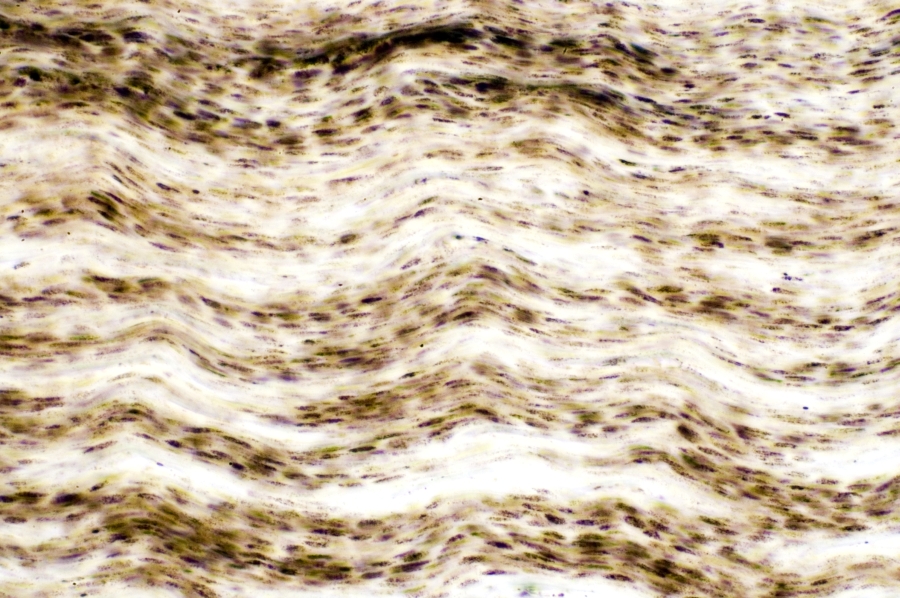

Image Filename: 62954_2135-B

62954_2135-B